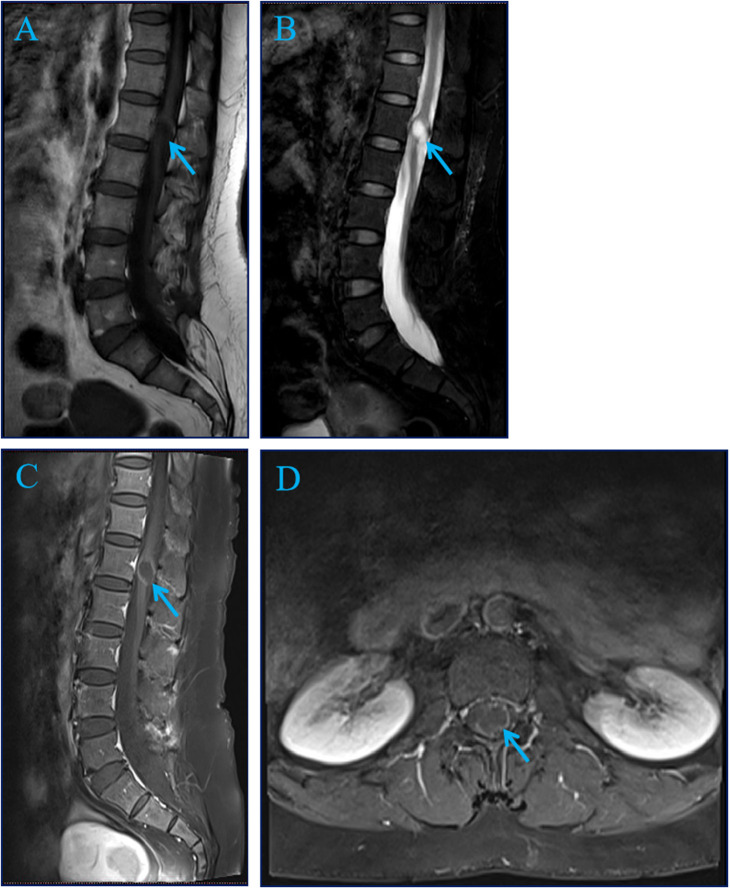

A 51-year-old female with a 10-year history of progressive low back pain presented with a 9 × 15 mm circular tumor adjacent to L1 on preoperative magnetic resonance imaging. The lesion was successfully removed by T12-L2 laminectomy and nail-rod fixation. Histopathological examination diagnosedmature intramedullary cystic teratoma. At 6-month follow-up, right lower limb numbness and pain were reduced.